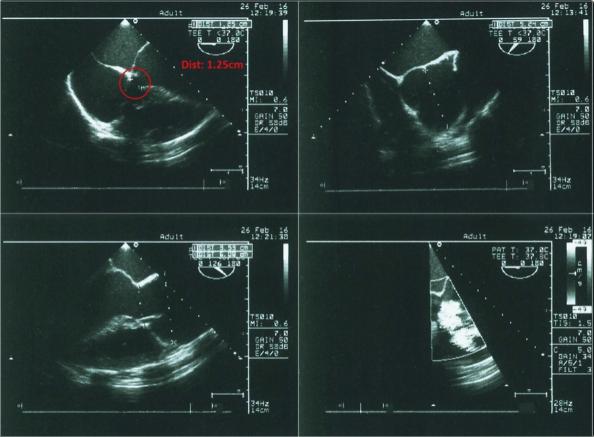

胸部X光显示心脏轮廓增大,提示左心室肥大。其他临床和实验室检查结果在正常范围内。经胸超声心动图显示膜周VSD、中度限制性分流(Qp/Qs=1.6)、AR和升主动脉瘤(图2)。经食道超声心动图证实了类似的发现(图3, 4)。

图4、经食管超声心动图